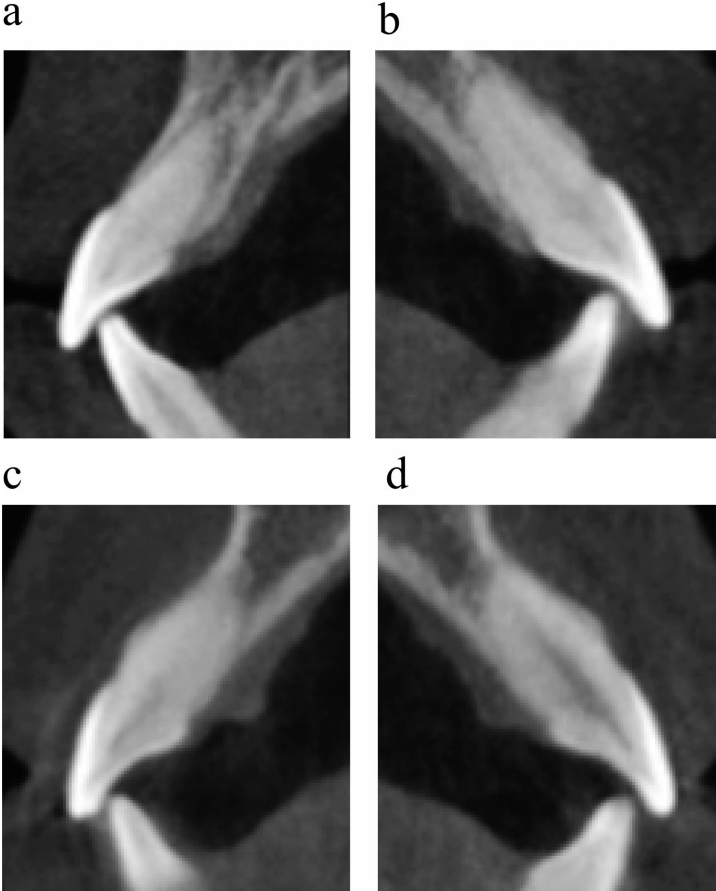

【治疗进展】研究团队首先通过13个月的TBA治疗重建后牙支撑,期间配合垂直牵引加速磨牙萌出。影像学监测显示,治疗过程中后牙咬合接触面积逐步增加,前牙咬合力显著降低。进入第二阶段后,采用Damon自锁托槽系统配合IZC微种植体,历时37个月完成牙列排齐和咬合精细调整。

【治疗结果】最终疗效令人振奋:上颌中切牙探诊深度(PPD)从7.3mm降至3.5mm,边缘骨水平(MBL)提升1.85mm,骨缺损面积(BDRD)减少3.6mm2。头影测量显示ANB角从4.6°降至3.6°,上切牙唇倾角(U1-SN)从120.4°矫正至100.9°,面型明显改善。三维影像证实牙根回到牙槽骨中央位置,咬合接触分析显示前牙创伤性接触完全消除。